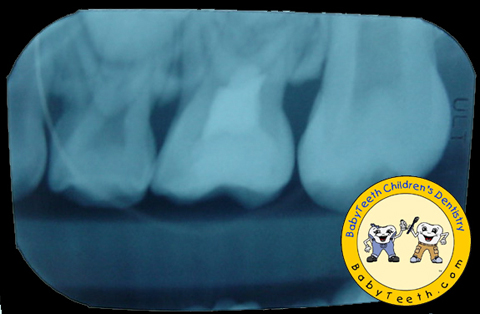

Radiographs taken before treatment.

Before Photo

Large decay on maxillary

2nd primary molar